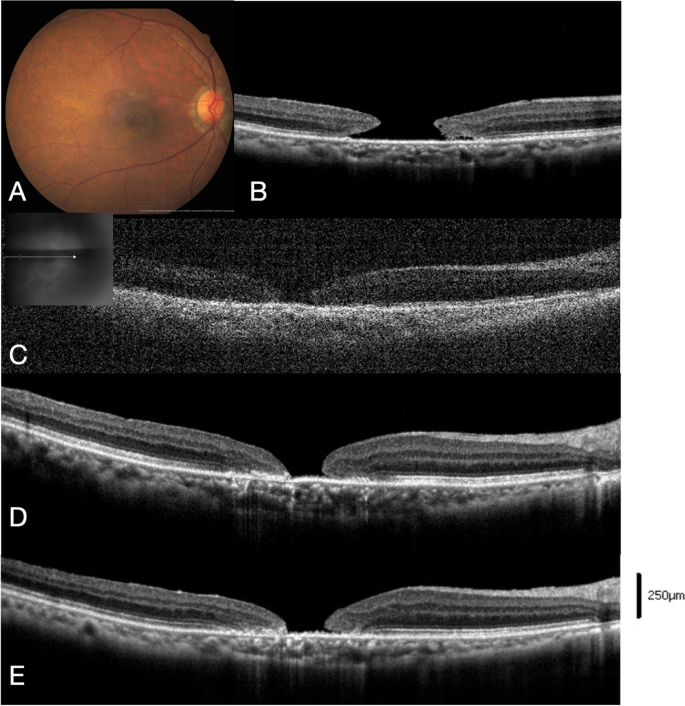

Twelve of 19 (63%) eyes achieved MH closure after IVI C3F8 (MH closure group). The other 7 eyes indicated persistent MHs after IVI C3F8 (MH open group). Three cases of the MH closure group (cases 5, 6, 9) and 1 case of the MH open group (case 17) underwent IVI C3F8 more than once. The representative cases of the 2 groups (cases 5 and 17) are presented in Figs. 2 and 3, respectively.

Case demonstration of case 5 in the MH closure group. A, B Preoperative color fundus and OCT image of the stage 3 MH with minimal diameter 531 μm. The MH base diameter was 1208 μm, and the height of MH margin was 390 μm. The patient received 23G pars plana vitrectomy, ILM peeling, IVI C3F8, and cataract surgery during the same operation. C At 12 days after the primary surgery, a 135 μm early persistent MH was noted by OCT image. IVI C3F8 0.2 mL was administered, and the patient was kept in the prone position with face down. D At 20 days, MH size decreased to 89 μm. E At 2 months, MH closure and foveal gliosis were noted. F, G At 6 months, the foveal contour restored with focal interruption of the outer ellipsoid zone layers. The BCVA improved from 20/400 preoperatively to 20/50 6 months after surgery

Case demonstration of case 17 in the MH open group. A, B Preoperative color fundus and OCT image of stage 4 MH (minimal diameter 657 μm, basal diameter 1285 μm). The margin of the hole was not elevated, and the margin height was 189 μm. C At 17 days after primary vitrectomy, ILM peeling, and IVI C3F8 0.6 mL, a 371-μm early persistent MH was noted. Intravitreal injection of C3F8 0.2 mL was performed. The image quality was influenced by the intravitreal gas–fluid interface. D At 1 month, the MH hole remained open. A second intravitreal injection of C3F8 0.2 mL was added. E At 5 months, the MH showed no closure and the edge sealed